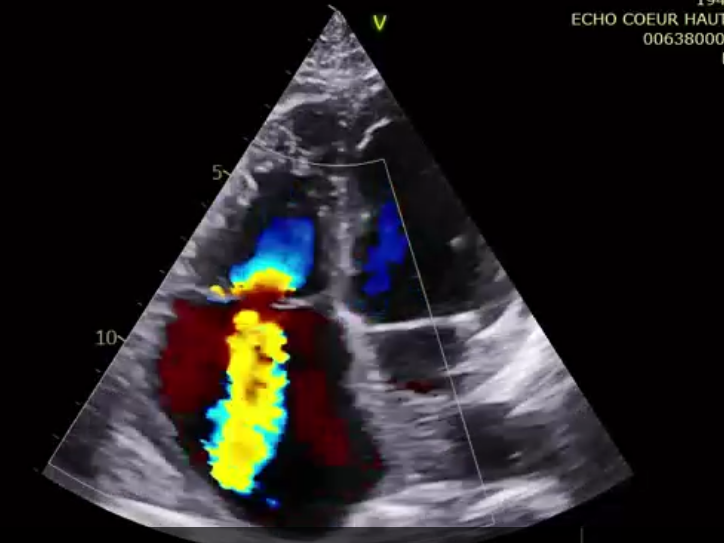

第一名患者是一位83歲的女性,術(shù)前TTE診斷TR等級4+,既往有高血壓和持續(xù)性房顫的病史。術(shù)者通過右頸靜脈入路的方式將輸送系統(tǒng)送入右心房,在DSA和TEE的引導(dǎo)下對輸送系統(tǒng)進(jìn)行調(diào)彎和推送,將輸送系統(tǒng)送至右心室目標(biāo)位置,接著調(diào)整其同軸性,使輸送系統(tǒng)在多個(gè)超聲引導(dǎo)平面下都垂直于三尖瓣瓣環(huán)。隨后開始釋放主體支架,錨定片與夾持件放出后,在TTE的引導(dǎo)下確認(rèn)了兩個(gè)夾持件分別在三尖瓣前葉和后葉的瓣下,且支架整體深度合適后,術(shù)者完整地釋放出整體支架。術(shù)者在DSA和TEE引導(dǎo)下確認(rèn)了錨定片完美貼合室間隔,再次確認(rèn)了瓣膜位置與同軸性良好后,通過獨(dú)有的錨定針將錨定片與室間隔固定,接著將瓣膜與輸送系統(tǒng)解離,完成手術(shù)。術(shù)后即刻瓣膜形態(tài)穩(wěn)定,輕微反流殘留,反流下降2+以上?;颊咝g(shù)后七天復(fù)查,經(jīng)胸超聲檢查提示患者右心功能明顯改善,僅可見輕微反流。

術(shù)后超聲提示微量瓣周漏